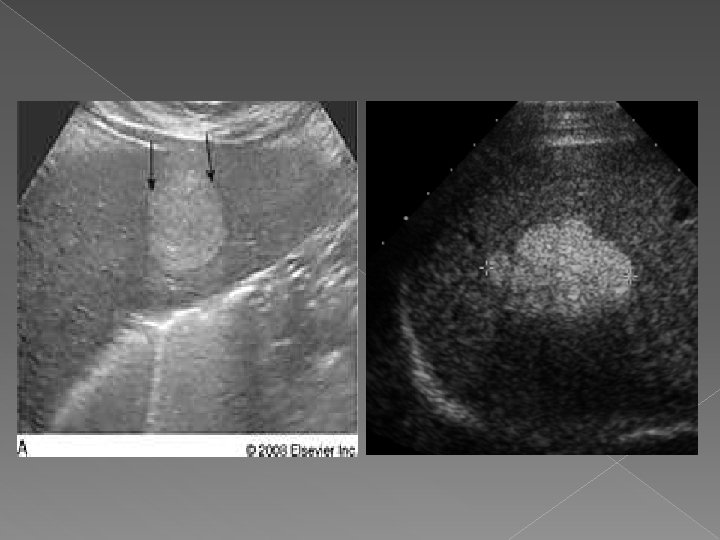

Chiste

Ultrasonografia : -uzuala, rapida, accesibila, informativa; -ideala pentru leziuni focale cu continut fluid; -tumorile solide sint mai greu de diferentiat. Scintigrafia: -rezultate bune in indentificarea leziunilor focale; -are valoare in aprecierea volumului si configuratia hepatica; -slaba specificitate.